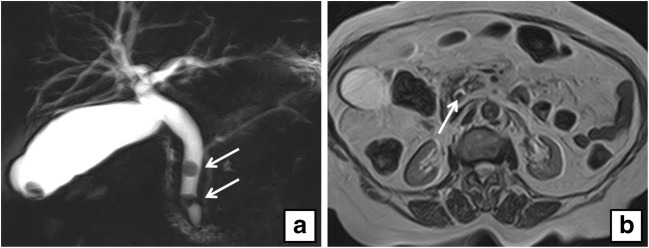

On preoperative US examination, 5 out of 104 patients demonstrated a dilated CBD and, among them, only one patient (20%) presented CBD lithiasis on MRCP, whereas 6 out of 99 patients (6%) with normal choledocal diameter showed CBD lithiasis (Figs. 1, 2, 3, and 4).